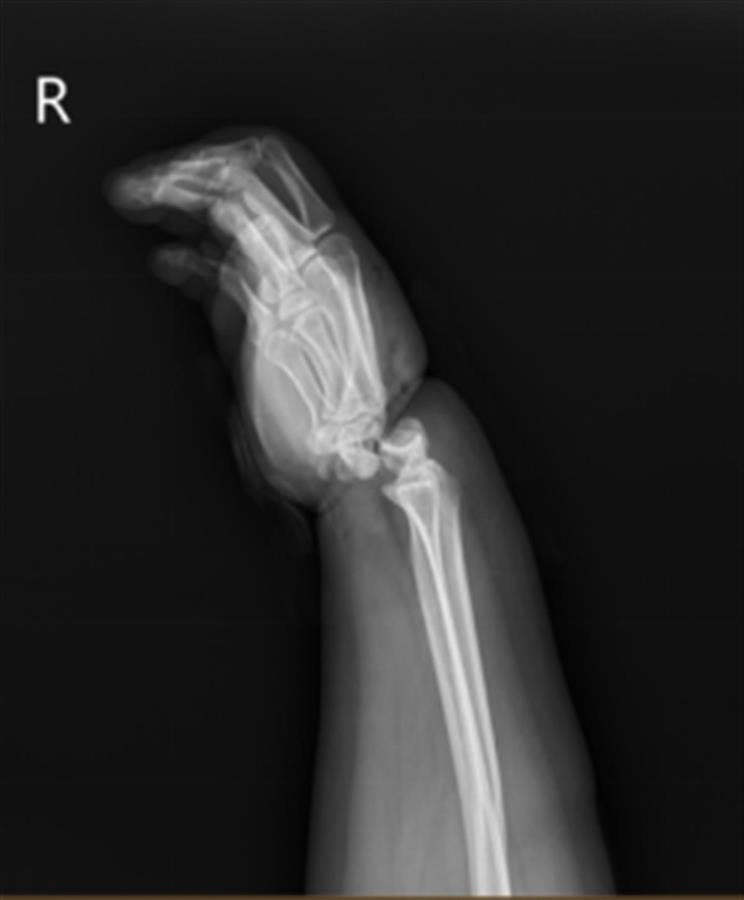

小美手部的X线摄片(图源:宁波二院供图)

“我刚看到这位患者时,她的右手十分肿胀,手腕严重变形,被绳勒过的皮肤已坏死,整个手掌因缺血呈现青紫色。”宁波二院手显微修复外科副主任郭宗慧向澎湃新闻介绍,经检查发现,小美的腕关节受暴力绞压,两条动脉血管已断,并伴有长段血管损伤,静脉血管出现长段栓塞,手腕关节已完全骨折脱位,有近1cm宽的环形皮肤被挤压坏死。